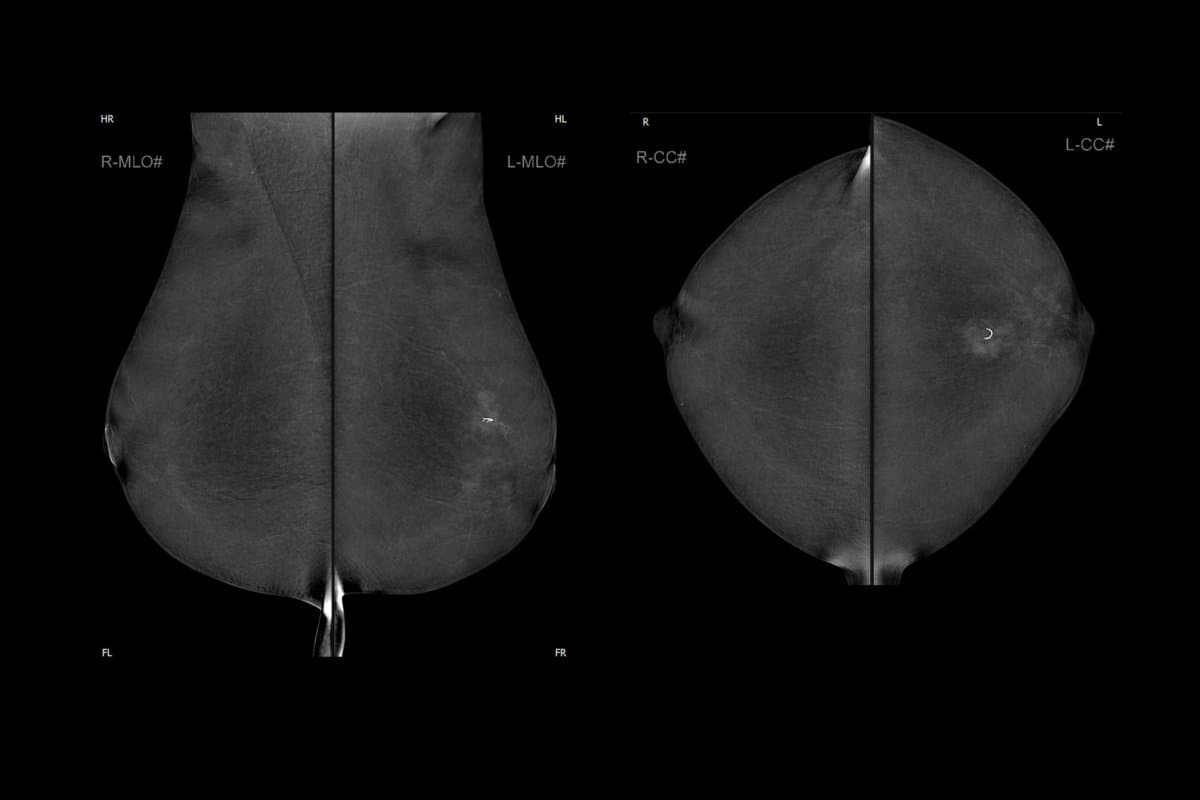

Die Mammographie ist der absolute Standard, wenn es zur Brustkrebs-Vorsorgeuntersuchung kommt. Inzwischen steht mit der Kontrastmittel-Mammographie (KM-MG) eine neuere Variante zur Verfügung, die zeitnah zur Diagnosesicherung beiträgt. Dieses Tool wird zurzeit allerdings nur bei vorliegendem Verdachtsfall eingesetzt.

In Österreich wird die Brustkrebs-Vorsorgeuntersuchung für alle Frauen ab dem 45. Lebensjahr empfohlen. Für Frauen mit erhöhtem Risiko – aufgrund von familiären genetischen Erkrankungen oder individueller Vorbelastung – kann die Testung bereits früher durchgeführt werden. Grundsätzlich wird die klassische Mammographie für diese Vorsorgeuntersuchung eingesetzt.